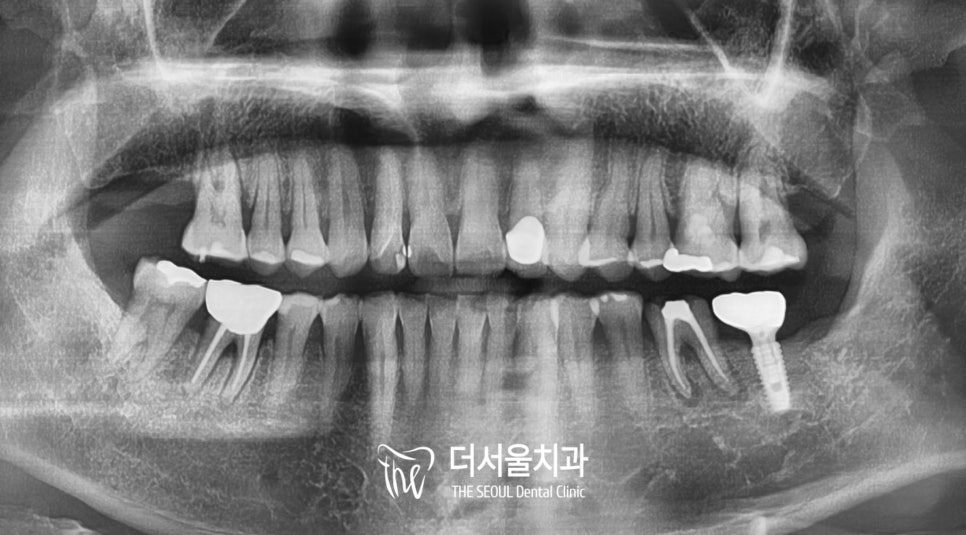

병원에 오게 되면

처음으로 찍게 되는

구강 파노라마 입니다.

자, 이 사진에서 없는 치아가

어디인지 아시겠습니까?

그동안 저의 포스팅을 즐겁게 보셨던 분들은

충분히 아실 거라고 생각합니다.

맞습니다!

오른쪽 위 맨 뒤 어금니가 없죠 ?

우리는 그걸 #17, 17번, 제2대구치 같은

여러 가지 이름으로 부르고 있습니다.

(모두 같은 말이니 어려워하지 마세요 ^^)